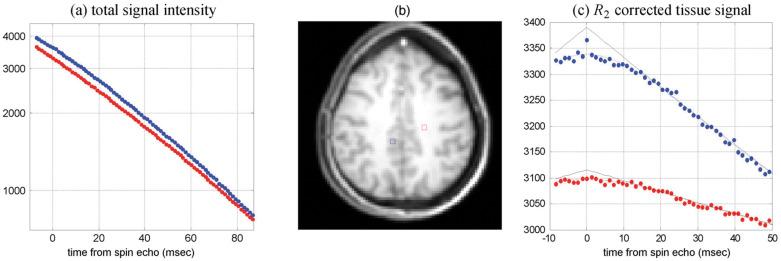

The metabolic rate of oxygen (MRO) is fundamental to tissue metabolism. Determination of MRO demands knowledge of the arterio-venous difference in hemoglobin-bound oxygen concentration, typically expressed as oxygen extraction fraction (OEF), and blood flow rate (BFR). MRI is uniquely suited for measurement of both these quantities, yielding MRO in absolute physiologic units of µmol O min/100 g tissue. Two approaches are discussed, both relying on hemoglobin magnetism. Emphasis will be on cerebral oxygen metabolism expressed in terms of the cerebral MRO (CMRO), but translation of the relevant technologies to other organs, including kidney and placenta will be touched upon as well. The first class of methods exploits the blood's bulk magnetic susceptibility, which can be derived from field maps. The second is based on measurement of blood water T, which is modulated by diffusion and exchange in the local-induced fields within and surrounding erythrocytes. Some whole-organ methods achieve temporal resolution adequate to permit time-series studies of brain energetics, for instance, during sleep in the scanner with concurrent electroencephalogram (EEG) sleep stage monitoring. Conversely, trading temporal for spatial resolution has led to techniques for spatially resolved approaches based on quantitative blood oxygen level dependent (BOLD) or calibrated BOLD models, allowing regional assessment of vascular-metabolic parameters, both also exploiting deoxyhemoglobin paramagnetism like their whole-organ counterparts.

氧代谢率(MRO)是组织代谢的基础。要确定 MRO,需要了解血红蛋白结合氧浓度的动静脉差异,通常以氧提取分数(OEF)和血流速率(BFR)表示。MRI 非常适合测量这两个量,以绝对生理单位(每 100 克组织 100 微摩尔氧/分钟)测量 MRO。本文讨论了两种方法,都依赖于血红蛋白的磁性。重点将放在以脑 MRO(CMRO)表示的脑氧代谢上,但也将涉及将相关技术转化为其他器官,包括肾脏和胎盘。第一类方法利用血液的整体磁化率,可以从磁场图中得出。第二种方法基于测量血液水 T1,这受红细胞内和周围局部诱导场中的扩散和交换调制。一些整体器官方法可以实现足够的时间分辨率,以允许在扫描器中进行脑能量学的时间序列研究,例如在脑电图(EEG)睡眠阶段监测的同时进行睡眠。相反,为了提高空间分辨率,已经开发出了基于定量血氧水平依赖(BOLD)或校准 BOLD 模型的空间分辨率方法,允许对血管代谢参数进行区域评估,这些方法也像它们的整体器官对应物一样利用去氧血红蛋白的顺磁性。